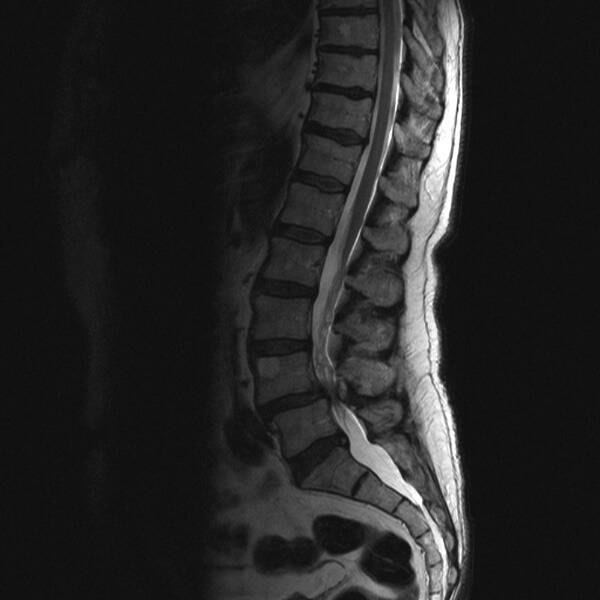

추간판탈출증

추간판탈출증은 추간판이 돌출되어 요통 및 신경 증상을 유발하는 질환이다. 즉, 추간판 내부의 젤리 같은 수핵이 탈출하여 주변을 지나는 척추신경을 압박함으로써 다양한 신경학적 이상 증상을 유발한다. 우리에게 "디스크"라고 잘 알려진 질환이 바로 추간판탈출증이며, 주로 점진적 퇴행과 관련이 있어 정상적인 노화 과정이나 외상에 의해 발생한다.